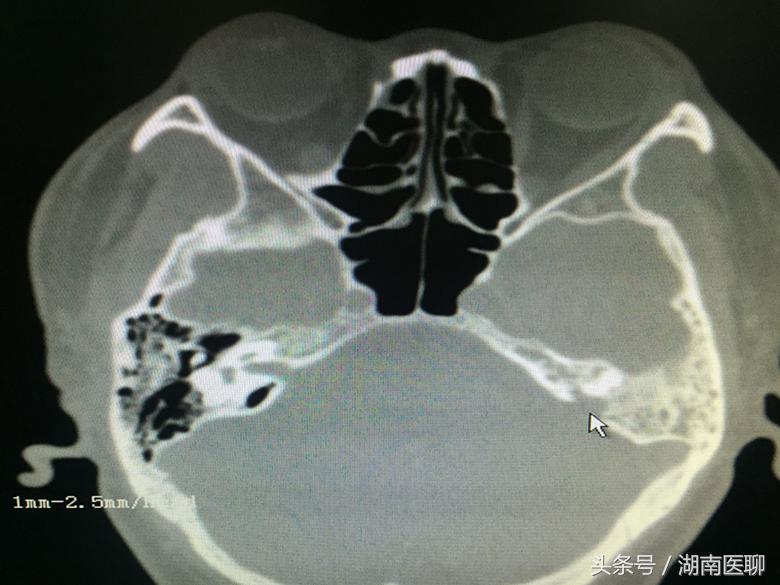

(影像资料上可以清楚地看到瘘口(鼠标所指位置))

通过核磁共振、CT检查发现,导致他多年来反复流清鼻涕、发热、脑膜炎的罪魁祸首竟然是脑膜穿孔

脑脊液从穿孔处漏到耳内,然后经中耳与鼻腔通道进入鼻咽部,低头时以“清鼻涕”方式流出。